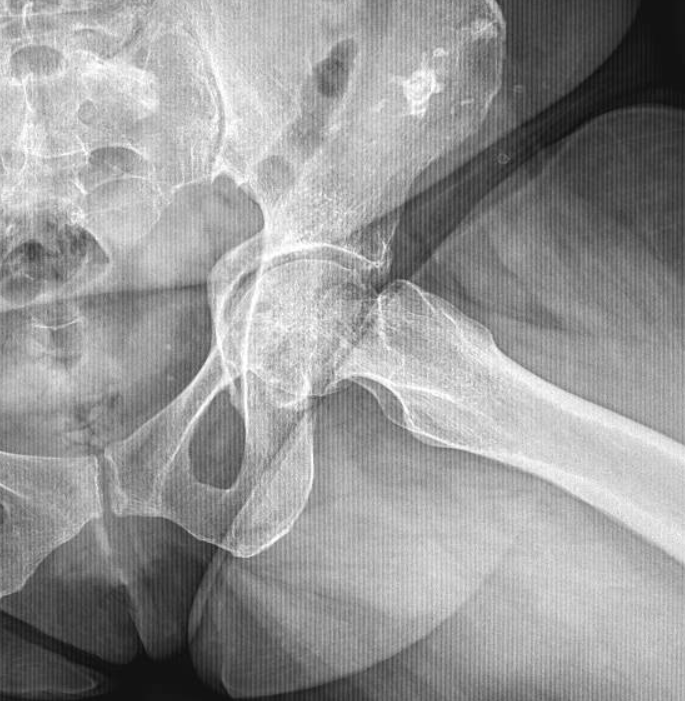

9/10/2025. 🟥🦴 What do you see here? (AP pelvis X-ray) Notice the altered trabecular pattern in the right femoral head — with a subtle articular collapse and a well-defined subchondral lytic lesion with sclerotic margins. Any guesses? 👀 #Radiology #MedTwitter

JuanMiranda tweet media

English